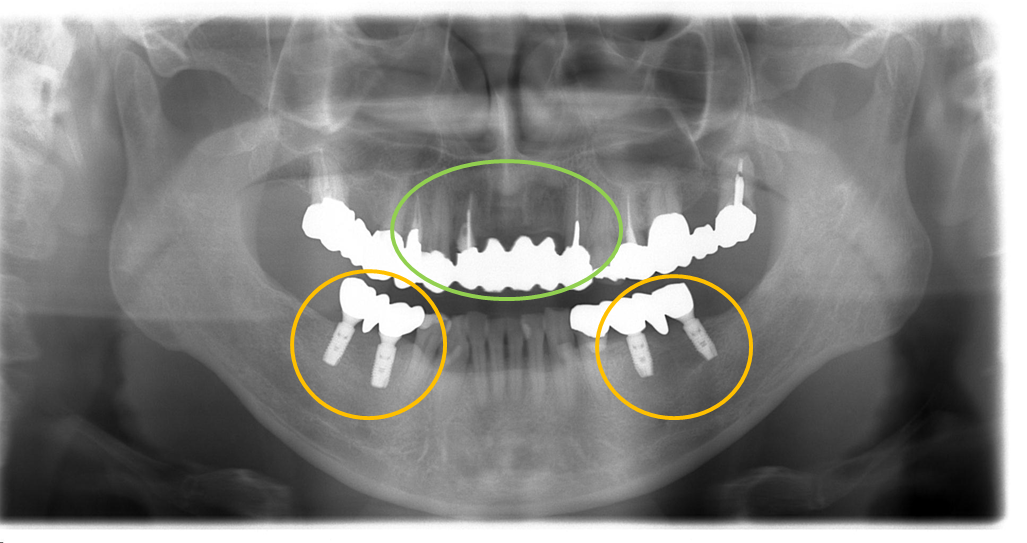

術後のエックス線写真です。

下顎にそれぞれ2本ずつインプラントを埋入し、金属冠(インプラント同士のブリッジ)を装着しました。(技工:S.Yonehara)

問題なくインプラントが埋入されています。

歯周病の問題もなく、4か月ごとのメインテナンスを行っています。